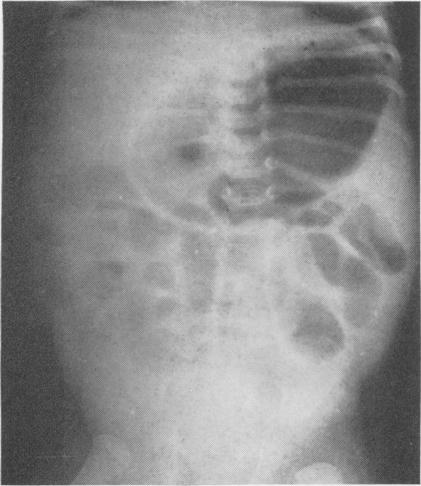

Gastric and intestinal obstructions in the newborn and infants; clinical review of 61 cases.

J Natl Med Assoc. 1958 Jan;50(1):36-9.